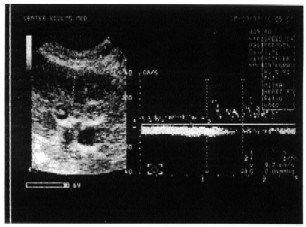

Рисунок 16. Динамика индекса минутного интеграла скорости кровотока в восходящей аорте

до (1) и во время выполнения бхуджангасаны (2) (n=10).

Рисунок 17. Кровоток в восходящей аорте

до (а) и во время выполнения бхуджангасаны (б)

Изменения минутного индекса интеграла кровотока в восходящей аорте (Flow/BSA, см/мин·м?) можно считать аналогичным сердечному индексу. У всех без исключения лиц во время выполнения позы этот параметр снизился (рис.16). Из этого мы вправе сделать вывод о том, что при ней падение ударного объема левого желудочка столь значительно, что, несмотря на развивающуюся тахикардию, минутный объем кровообращения существенно снижается (рис. 17).